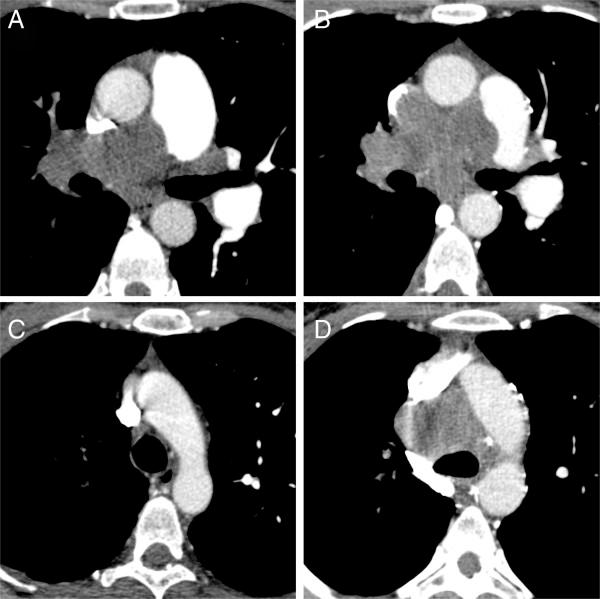

The median interval between the first imaging study and the final diagnosis was 11 weeks (0-12 weeks). The most frequently observed imaging findings suggestive of malignant disease in patients with sarcomas of the pulmonary arteries were a large filling defect with vascular distension, unilaterality and a lack of improvement despite effective anticoagulation. In patients with aortic sarcomas we most frequently observed a pedunculated appearance and an atypical location of the filling defect. The F-18 FDG PET(/CT) examinations demonstrated an unequivocal hypermetabolism of the lesion in all cases (4/4). MRI proved lesion vascularization in 5/6 cases.

首次影像检查与最终诊断的中位间隔时间为11周(0 - 12周)。肺动脉肉瘤患者中最常观察到的提示恶性疾病的影像表现为伴有血管扩张的大充盈缺损、单侧性以及尽管进行了有效的抗凝治疗但仍无改善。在主动脉肉瘤患者中,我们最常观察到带蒂外观和充盈缺损的非典型位置。F-18 FDG PET(/CT)检查在所有病例(4/4)中均显示病变明确的高代谢。MRI在5/6例病例中证实了病变的血管化。